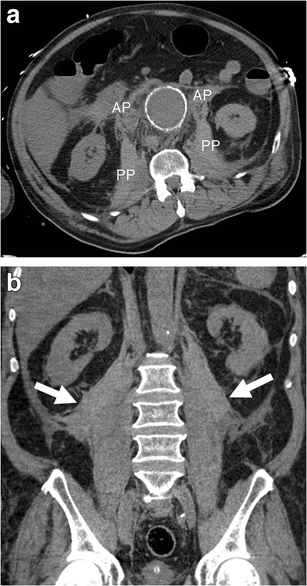

Retroperitoneal haematoma

Retroperitoneal haematoma. a Axial unenhanced CT image of a 72-year-old man demonstrates haemorrhage involving bilateral anterior (AP) and posterior (PP) pararenal spaces as well as the area along the psoas muscles. The left kidney is displaced laterally. Attenuation of 45 HU (more than 30 HU) indicates acute haematoma. b Coronal unenhanced CT image of the same patient shows bilateral retroperitoneal haematomas (white arrows)